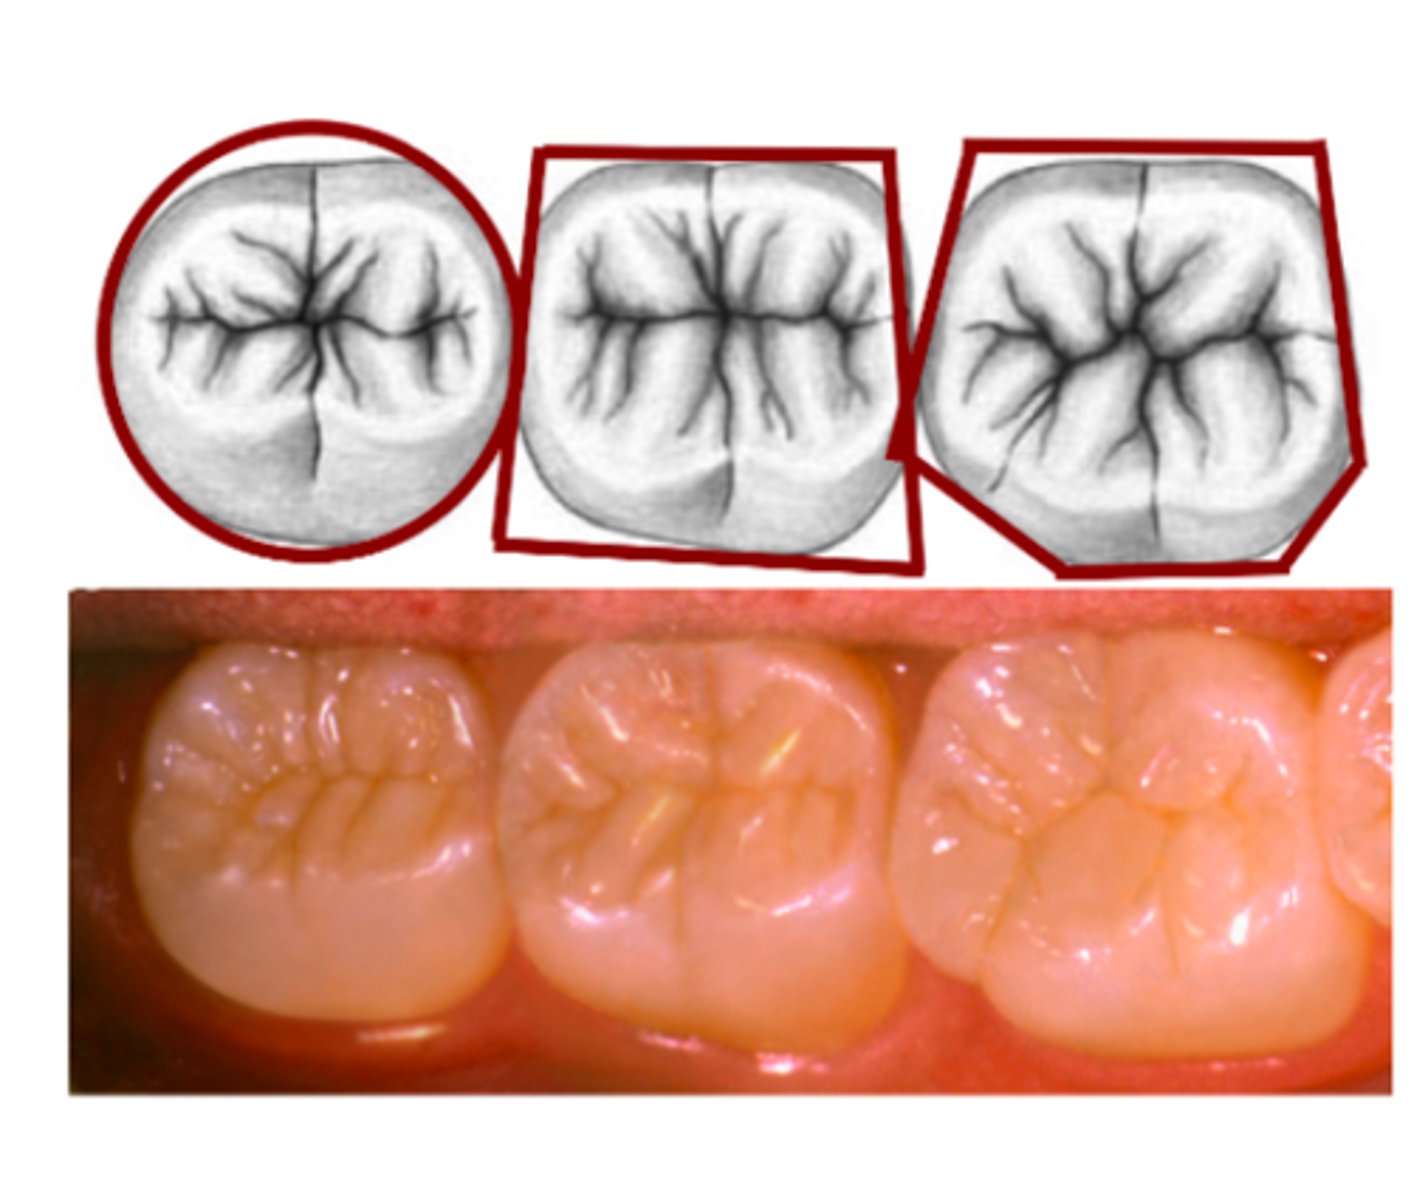

What is the occlusal crown outline?

Outer outline of the entire tooth crown from the occlusal view

What is the occlusal table?

occlusal surface that is bounded by the continuous cusp ridges & marginal ridges